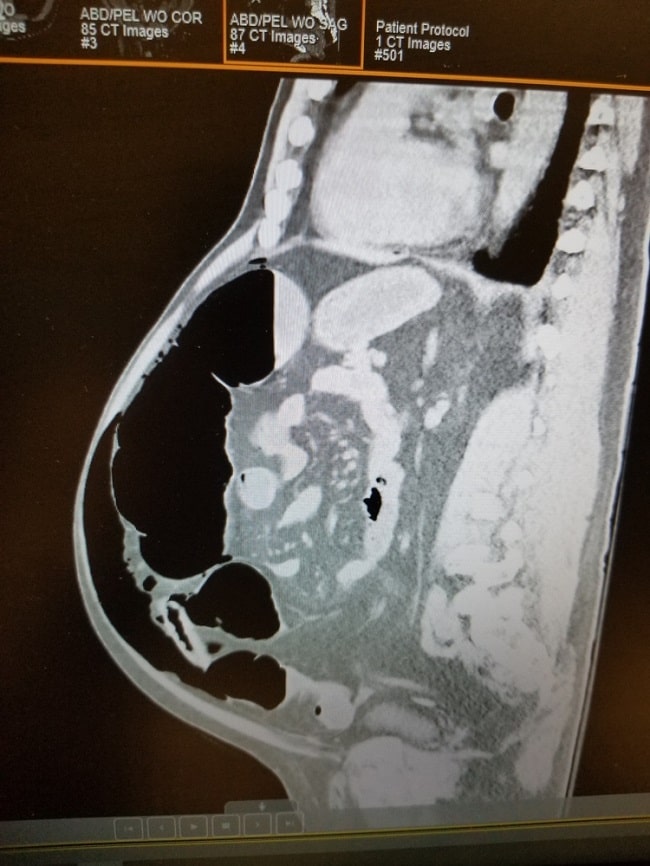

Rontgen abdomen biasanya menunjukkan dilatasi kolon signifikan, terutama pada caecum dan kolon asendens, tanpa tanda obstruksi distal. CT scan lebih baik dalam menggambarkan kolon yang distensi, mengidentifikasi penyebab lain yang mungkin, serta menilai risiko perforasi. Pemeriksaan elektrolit juga penting karena ketidakseimbangan, terutama hipokalemia atau hipomagnesemia, dapat memperburuk kondisi. Kolonoskopi kadang dilakukan jika diagnosis masih belum jelas atau untuk dekompresi kolon terapeutik.[9,10]

Pemeriksaan radiologi, seperti rontgen dan CT scan abdomen, dapat menunjukkan adanya dilatasi kolon signifikan tanpa bukti adanya obstruksi di bagian distal. Penatalaksanaan bergantung pada seberapa besar diameter usus pasien. Jika diameter usus diperkirakan <9 cm, maka terapi konservatif dapat dilakukan. Di sisi lain, jika diameter usus melebihi 12 cm, maka tindakan operatif umumnya diperlukan.